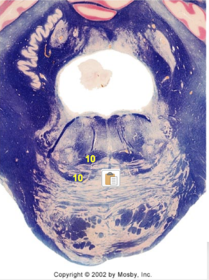

| Nucleus gracilis | |

| Accessory nucleus | |

| Medial longitudinal faciculus | |

| Pyramidal decussation | |

| Medullary pyramids | |

| Anterior spinocerebellar tract | |

| ALS | |

| Posterior spinocerebellar tract | |

| Spinal tract of V | |

| Spinal nucleus of V | |

| Nucleus cuneatus | |

| Fasciculus cuneatus | |

| Fasciculus gracilis | |

| Central canal | |